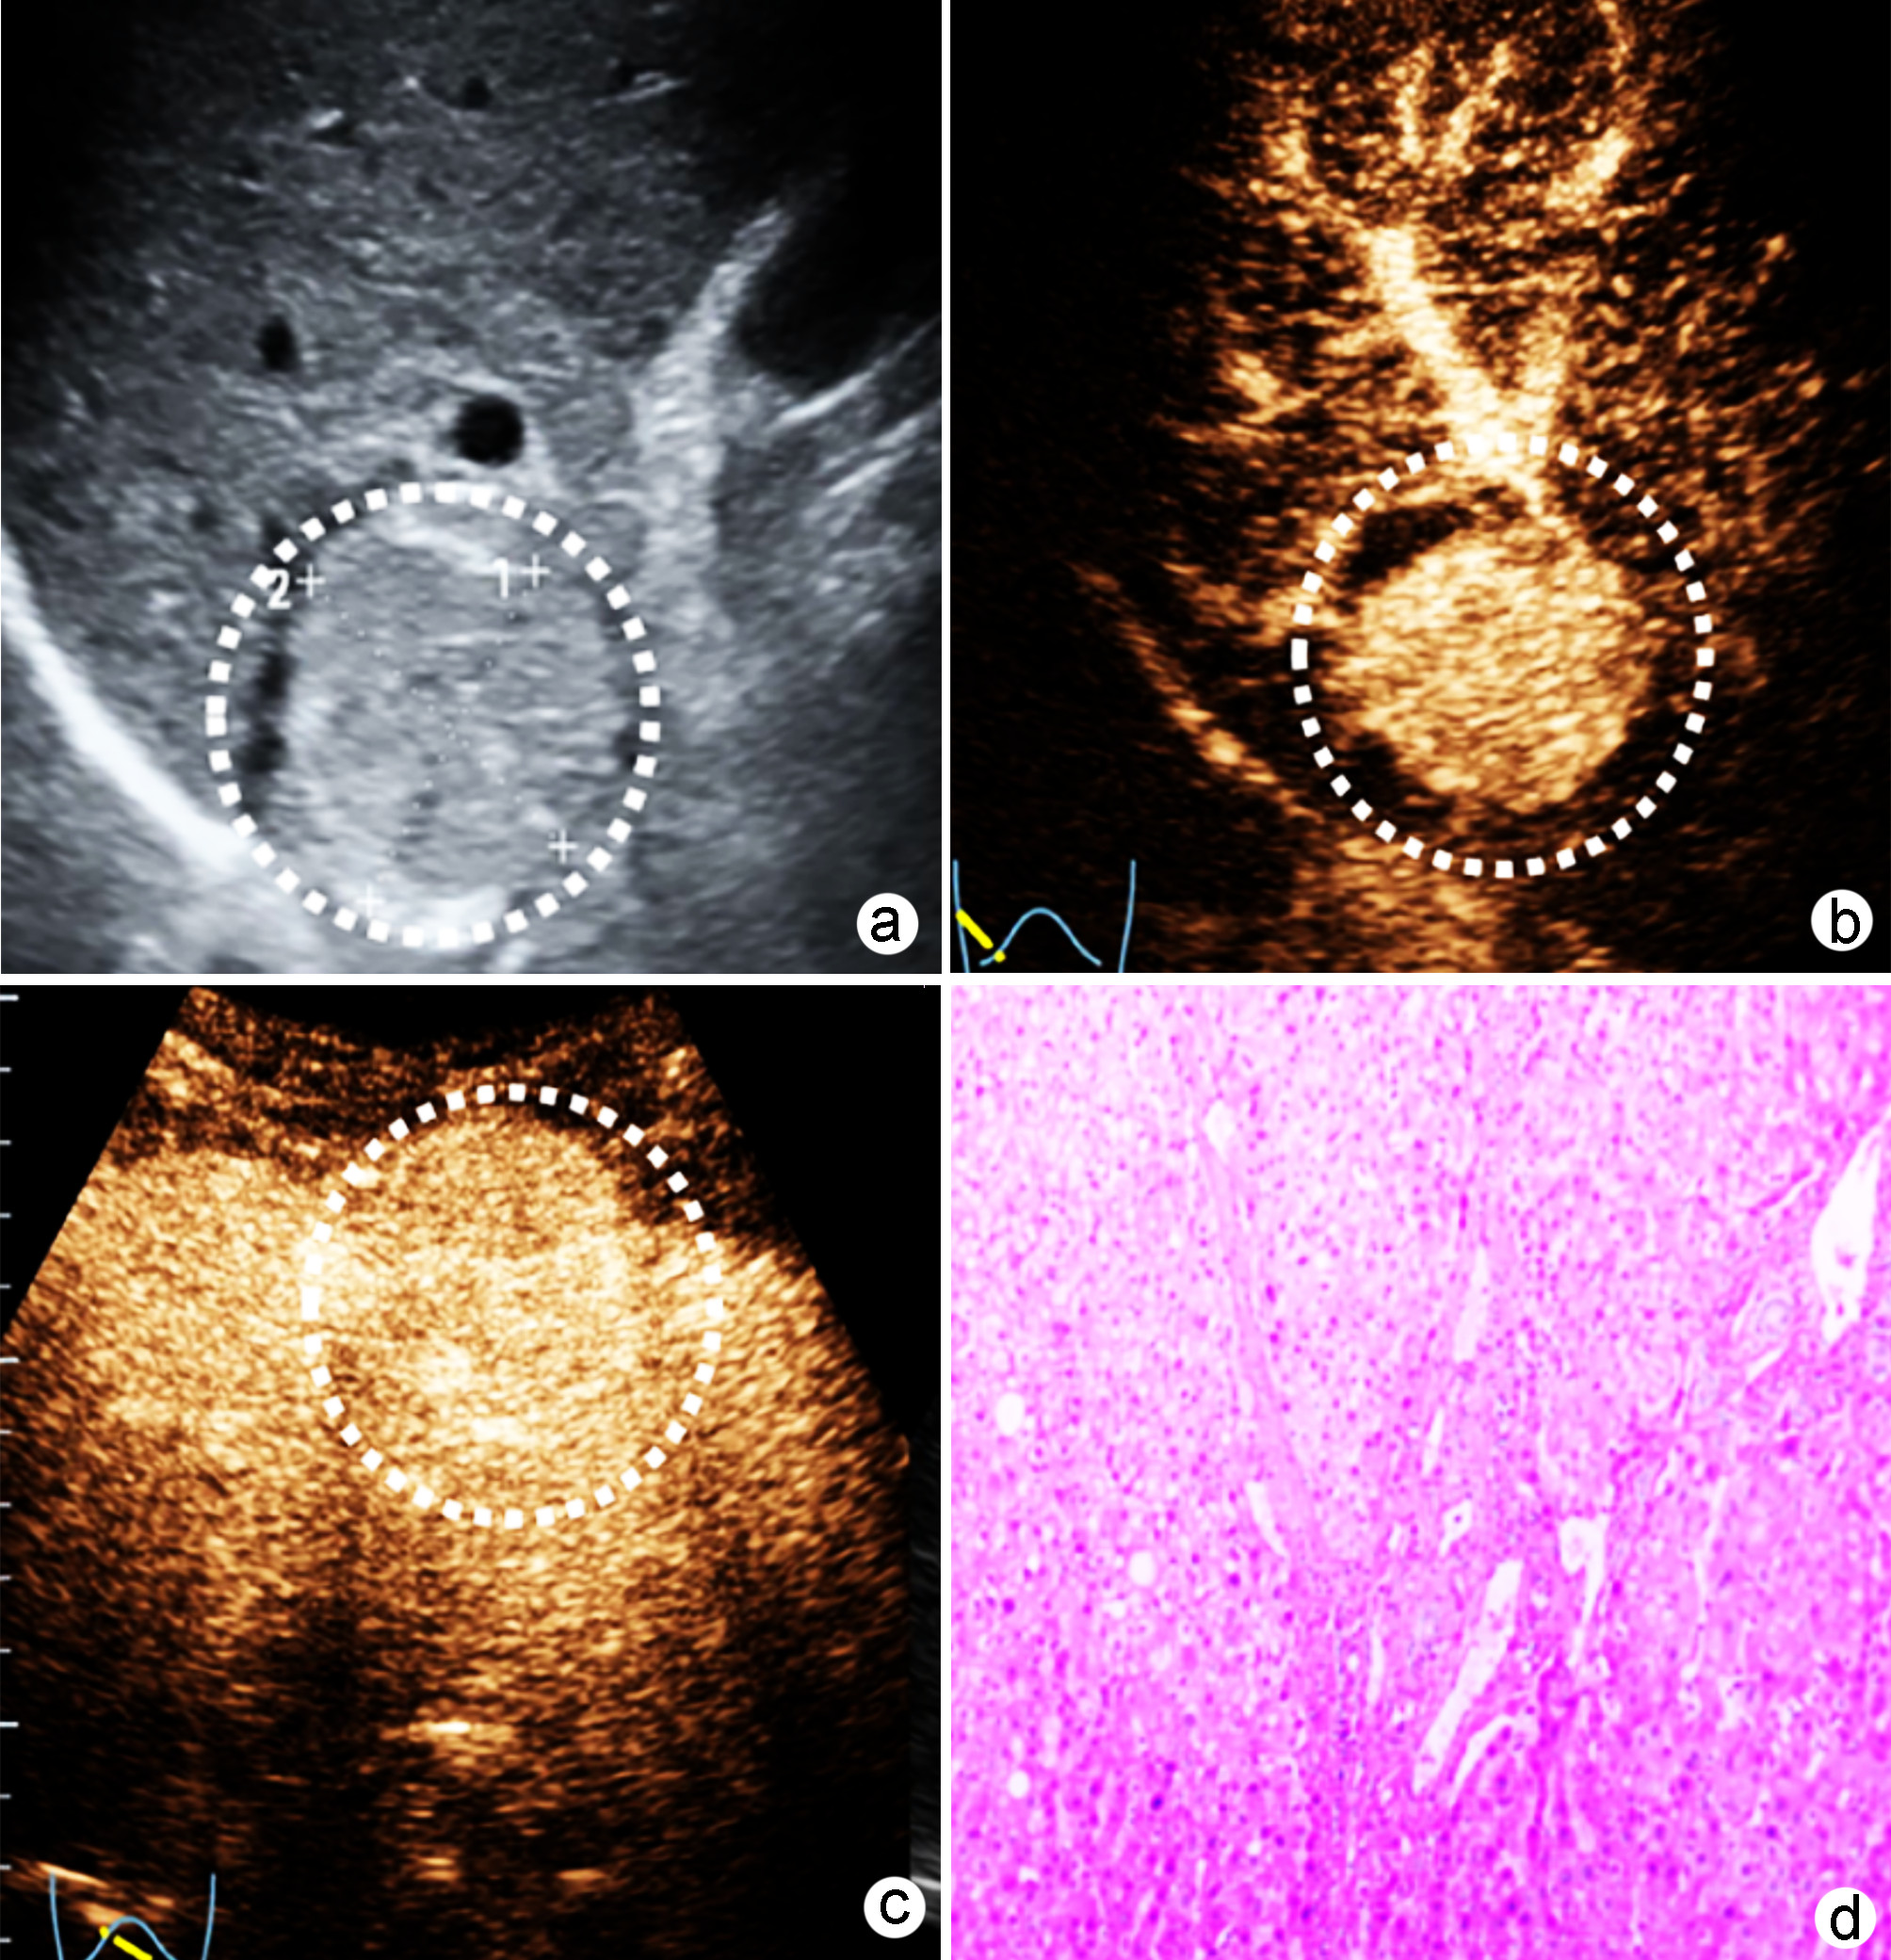

Construction and validation of a nomogram model for microvascular invasion in hepatocellular carcinoma based on the characteristics on contrast-enhanced ultrasound Liver Imaging Reporting and Data System

Jing XI, Meiqin GU, Zuowei BAO

2022, 38(11): 2520-2525. DOI: 10.3969/j.issn.1001-5256.2022.11.016

Abstract(849) HTML (325) PDF (2938KB)(46)

Abstract:

Objective  To construct and validate a nomogram model for predicting microvascular invasion (MVI) based on the characteristics on contrast-enhanced ultrasound (CEUS) Liver Imaging Reporting and Data System (LI-RADS) in patients with hepatocellular carcinoma (HCC).  Methods  A total of 262 patients with HCC who were diagnosed in Wujin Hospital Affiliated to Jiangsu University from January 2017 to July 2020 were enrolled and randomly divided into modeling group and validation group at a ratio of 1∶ 1, with 131 patients in each group. MVI was confirmed by postoperative microscopic pathological results, and there were 70 patients with MVI in the modeling group and 56 patients with MVI in the validation group. CEUS was used to evaluate LI-RADS characteristics for the two groups. The independent samples t-test was used for comparison of continuous data between the two groups, and the chi-square test was used for comparison of categorical data between the two groups. Univariate and multivariate Logistic regression analyses were used to identify the risk factors for MVI in the modeling group; the receiver operating characteristic (ROC) curve was plotted, and the area under the ROC curve (AUC) was calculated for the model in predicting MVI to evaluate the accuracy of prediction; a decision curve analysis was used to evaluate the consistency of the model, and dispersion was compared between the calibration curve and the standard curve for the model in predicting MVI.  Results  There were no significant differences in clinical data and CEUS findings between the modeling group and the validation group (all P > 0.05). The univariate analysis showed that compared with the MVI-negative patients, the MVI-positive patients had significant increases in serum alpha fetoprotein (AFP) level, tumor diameter, and LR-5 "late and mild washout" and LR-M "early washout" on LI-RADS, as well as a significantly higher LI-RADS grade (all P < 0.05). The multivariate analysis showed that AFP 20-400 ng/mL (odds ratio [OR]=2.65, P < 0.001), AFP≥400 ng/mL (OR=3.98, P < 0.001), tumor diameter ≥30 mm (OR=2.12, P < 0.001), and LR-M on CEUS (OR=3.24, P < 0.001) were independent risk factors for MVI. The ROC curve analysis showed that the nomogram had an AUC of 0.867 and 0.821 in predicting MVI in the modeling group and the validation group, respectively. The nomogram model had a C-Index of 0.765 (95% confidence interval: 0.701-0.834). The calibration curves of the nomogram model were close to the standard curve in both groups.  Conclusion  The nomogram model based on LI-RADS obtained by CEUS in combination with AFP and tumor diameter has a good application value and can guide the preoperative screening for patients at a high risk of MVI and the development of appropriate surgical plans in clinical practice.